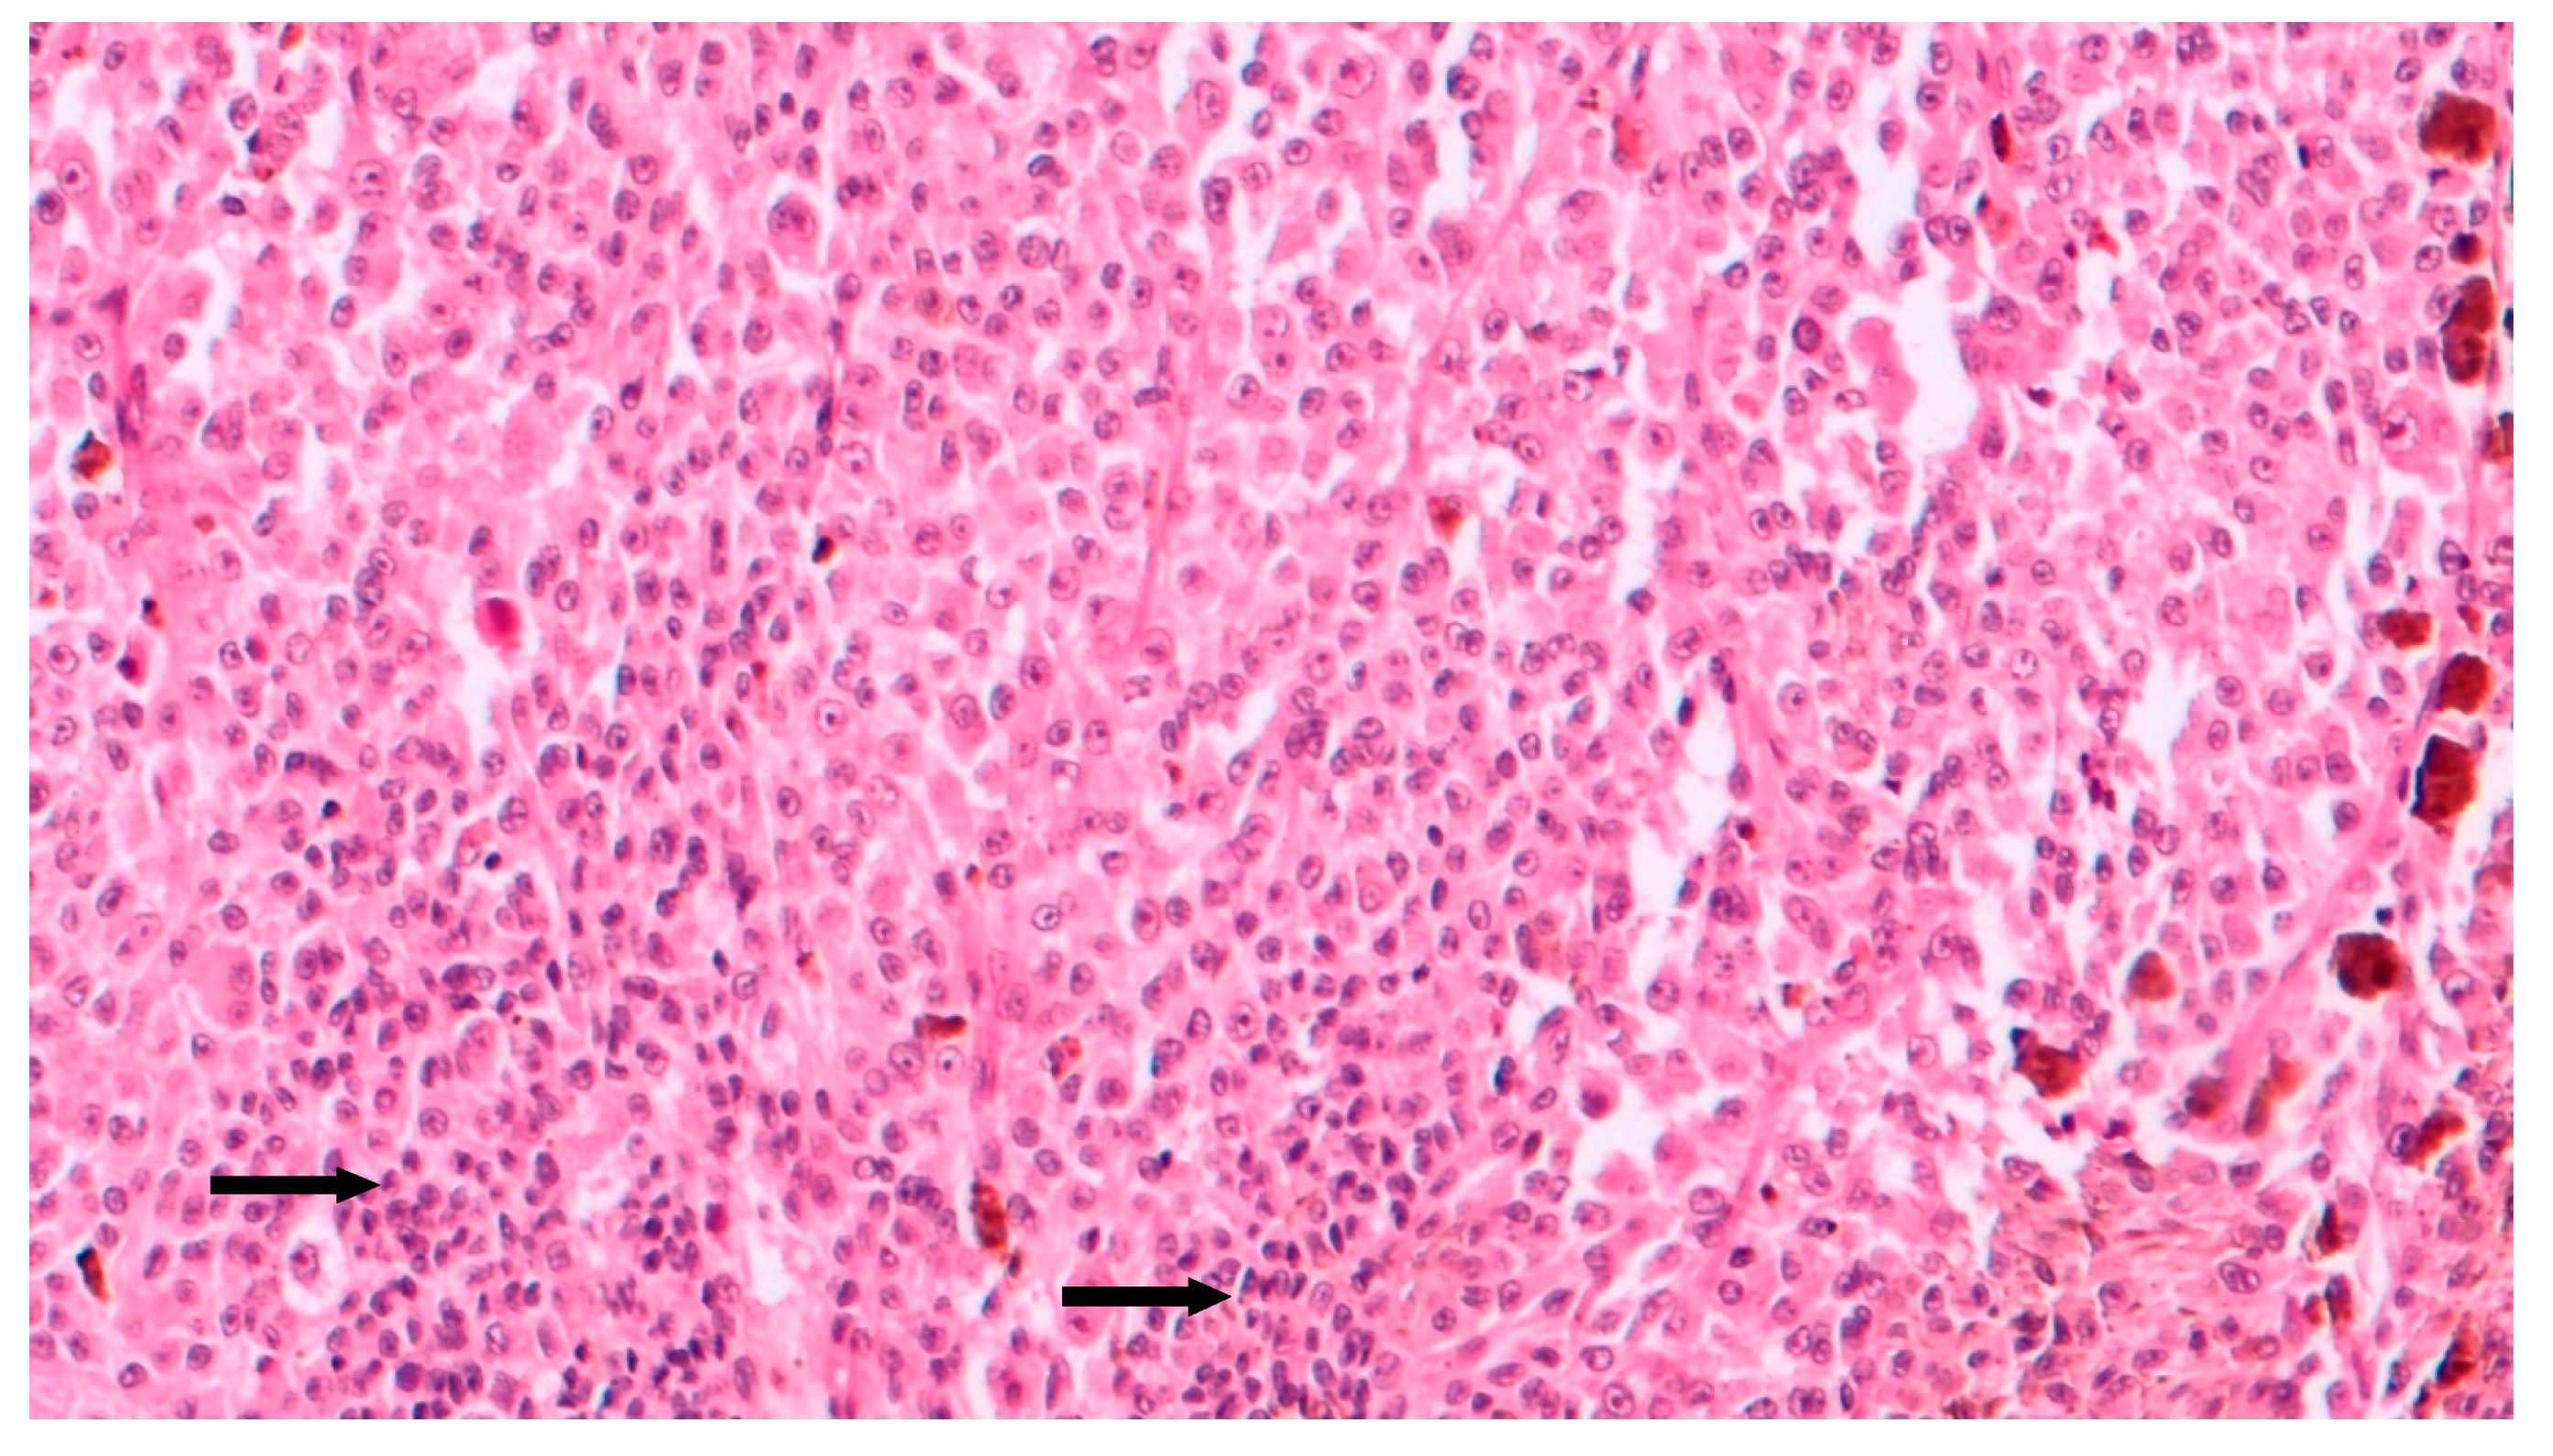

Figure 5.

Intermediate magnification showing epithelioid cell type choroidal melanoma with sparse chronic lymphocytic infiltrates (arrows) intermingled to neoplastic cells (hematoxylin and eosin; original magnification 100×).